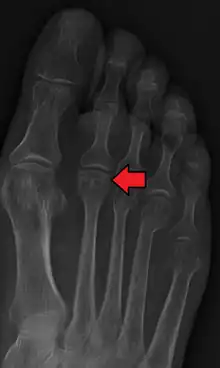

Diagnosis

Accurate diagnosis of Freiberg disease typically involves a combination of clinical examination and imaging studies:

- Radiography: X-rays may reveal flattening, sclerosis, or fragmentation of the metatarsal head.

- Magnetic Resonance Imaging (MRI): Provides detailed images of soft tissue and bone changes, particularly useful in early stages of the disease.